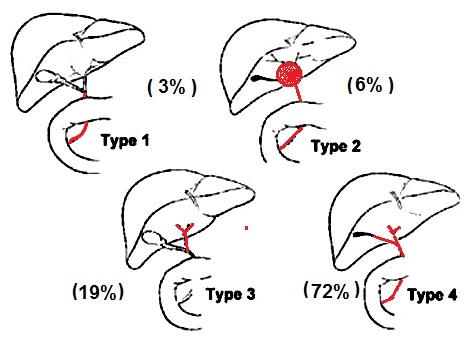

Classification de

Kasai de atresie de voie biliaire

- Type 1 atresie limite

au canal choledoque (3%)

- Type 2 Kyste du hile

hepatique et atresie de VP ( 6% )

- Type 3 Vesicule biliaire ,

canal cystique et canal choledoque sont

permeable ( 19%)

- Type 4 Atresie extrahepatique

complete ( 72% )